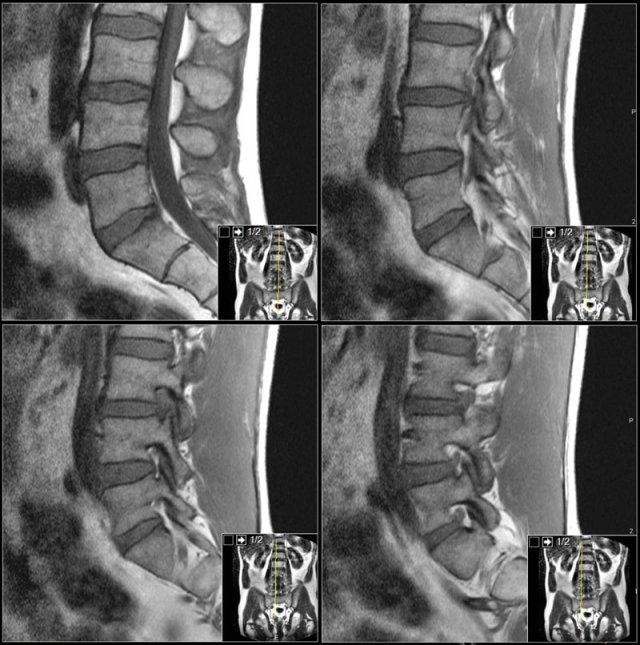

Các hình ảnh cắt dọc chuỗi xung T1W cung cấp nhiều thông tin chẩn đoán nhất.

Trước khi bắt đầu tìm kiếm bất kỳ thoát vị nào, hãy quan sát kỹ các mô trước cột sống và tủy xương.

Khi đã phát hiện bất thường, hãy đối chiếu các phát hiện này với hình ảnh chuỗi xung T2W (hình).

Trước tiên hãy quan sát các hình ảnh.

Nhấp để phóng to.

Sau đó tiếp tục đọc.

Các dấu hiệu bao gồm:

- Thoát vị đĩa đệm L3L4.

- Di trú lên phía trên.

- Chèn ép rễ thần kinh L3 trong lỗ liên hợp.

Trước tiên hãy cuộn qua các hình ảnh chuỗi xung T1W mặt phẳng đứng dọc này.

Các dấu hiệu là gì?